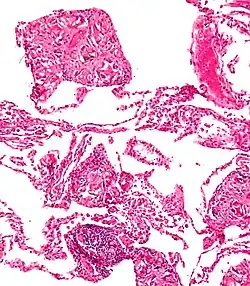

One of the most common locations for a foreign body is the alimentary tract.

It is possible for foreign bodies to enter the tract from the mouth or rectum.

Both children and adults experience problems caused by foreign objects becoming lodged within their bodies. Young children, in particular, are naturally curious and may intentionally put shiny objects, such as coins or button batteries, into their mouths. They also like to insert objects into their ear canals and nostrils.[1] The severity of a foreign body can range from unconcerning to a life-threatening emergency. For example, a coin causes local pressure on the tissue but generally is not a medical emergency to remove. A button battery, which can be a very similar size to a coin, generates hydroxide ions at the anode and causes a chemical burn in two hours.[2] An ingested button battery that is stuck in the esophagus is a medical emergency. In 2009, Avolio Luigi and Martucciello Giuseppe showed that although ingested nonmagnetic foreign bodies are likely to be passed spontaneously without consequence, ingested magnets (magnetic toys) may attract each other through children's intestinal walls and cause severe damage, such as pressure necrosis, perforation, intestinal fistulas, volvulus, and obstruction.[3]